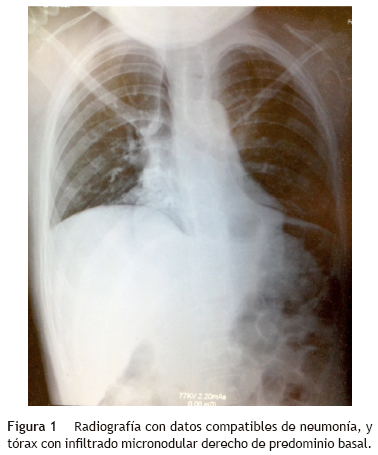

La radiografía simple mostró datos compatibles con neumonía: tórax con infiltrado micronodular derecho de predominio basal (fig. 1). Al realizarse tomografía de tórax con ventana pulmonar, esta mostró una imagen sugestiva de consolidación bilateral, basal y medial con broncograma aéreo, así como derrame pleural derecho sin compromiso de la función (<10%).